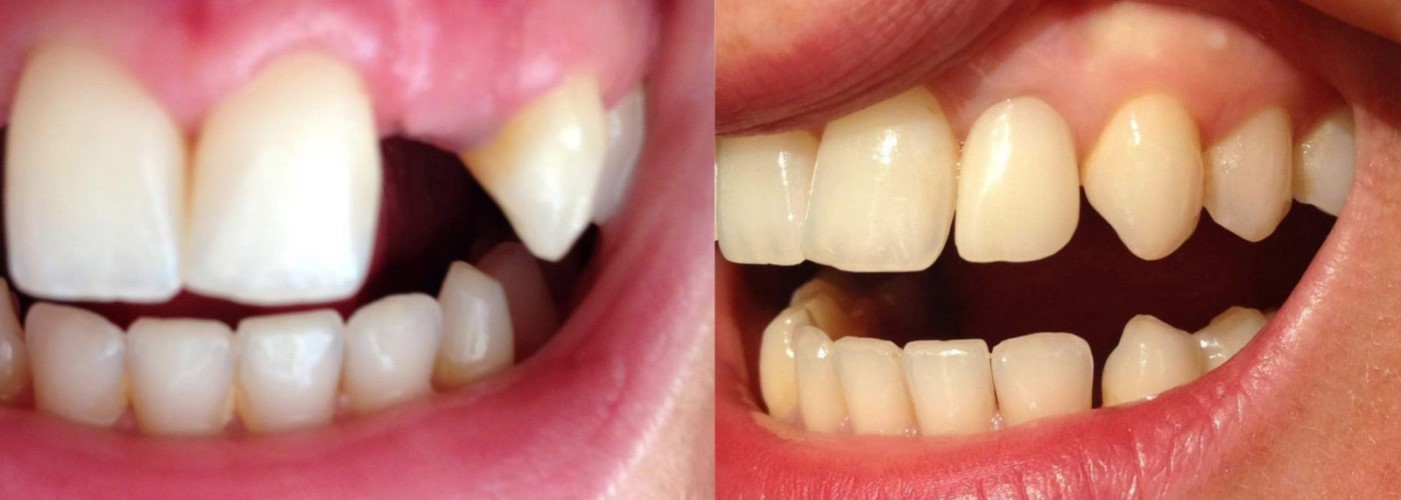

Estrazione di 4 incisivi inferiori compromessi, inserimento immediato di due impianti e applicazione di protesi provvisorie dopo una sola ora. A distanza di 5 mesi è stata protesizzata definitivamente con denti in ceramica.